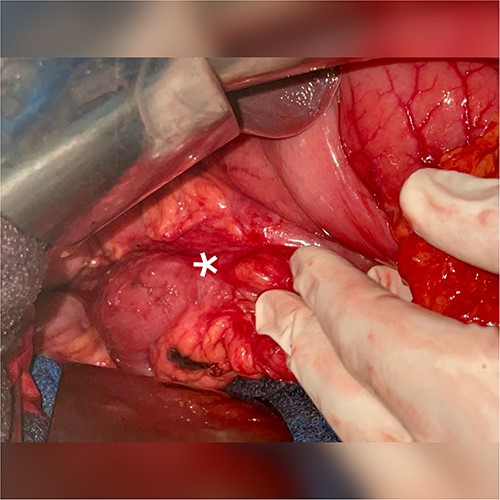

A 51-year-old patient with no significant medical history. He was admitted to the emergency department with abdominal distension, persistent vomiting, intolerance to solid foods, he could consume only small amounts of liquid. Clinical examination of the abdomen revealed diffuse tenderness in all quadrants, accompanied by severe abdominal distension. Prior to his consultation at our institution, he had undergone oesophagogastroduodenoscopy, revealing a dilated stomach and narrowing of the pyloric ring. Biopsies revealed the presence of H. pylori and S. ventriculi. (Fig. 1). He was put on conservative treatment for a duration of ~4 weeks, but no significant improvement was noted. On admission to our clinic, he underwent a computed tomography (CT) scan of the abdomen (Fig. 2), which revealed marked dilatation of the stomach, as well as an upright arrangement of the entire jejunal coves, suggesting the presence of a high occlusion due to a right anterior para-duodenal internal hernia. While a more comprehensive non-operative management approach could have been contemplated in the absence of hernia-related concerns, the clinical deterioration and the refractory nature of symptoms to medical therapy served to underscore the appropriateness of the surgical approach. During surgery, the hypothesis of a para-duodenal internal hernia was ruled out after a duodeno-pancreatic detachment using the KOCHER maneuver, thus facilitating exposure of the entire duodenum and also allowing individualization of the transition zone located at the level of the pylorus (Fig. 3), thus justifying the performance of gastroenteric anastomosis (Fig. 4). Post-operatively, the diet was progressively advanced and well tolerated. On discharge, the patient was in satisfactory condition.